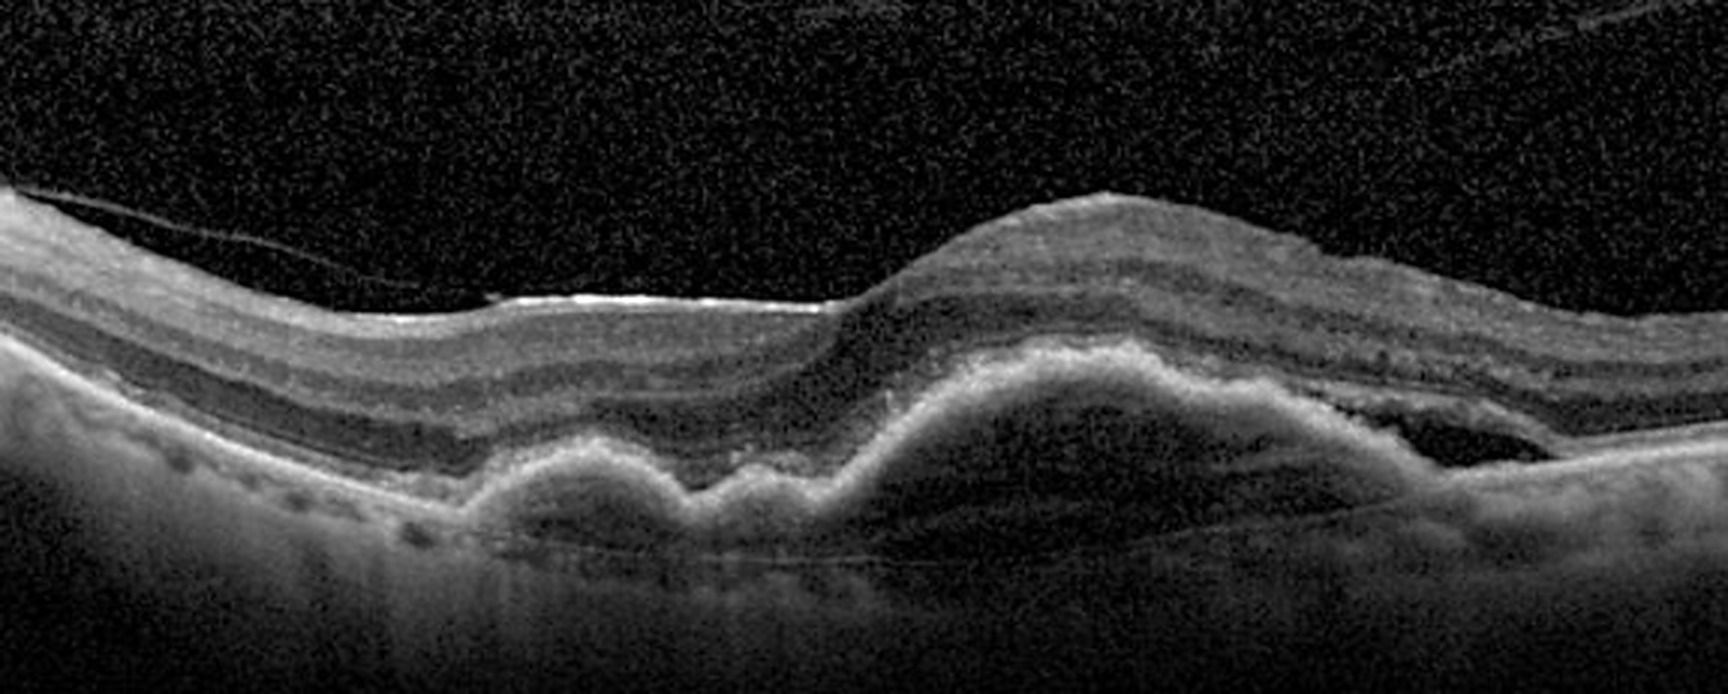

La dégénérescence maculaire liée à l'âge DMLA exsudative est une maladie chronique avec une activité cyclique présentant des périodes de rémission. Il n'existe pas de guérison possible. Une atteinte bilatérale est fréquente.